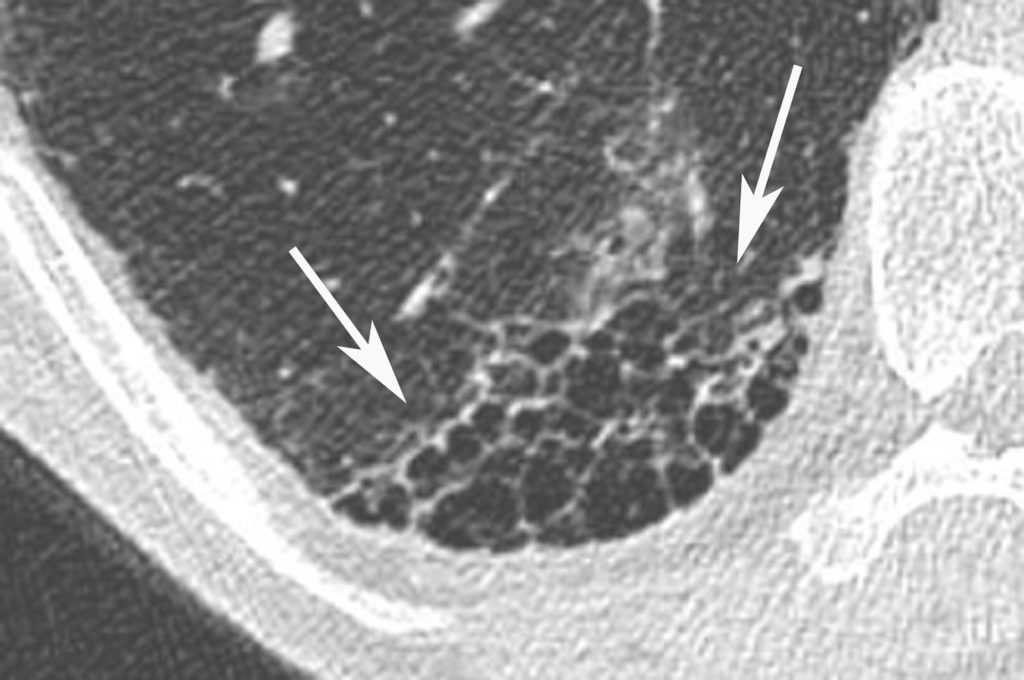

Fig. 97.8. Fibrose pulmonaire idiopathique.

Agrandissement sur la base droite. Poumon en « rayon de miel » dans la région sous-pleurale (flèches). Le contenu des kystes organisés en réseau est de densité aérique traduisant la destruction irréversible du parenchyme pulmonaire.

Source : CERF, CNEBMN, 2022.